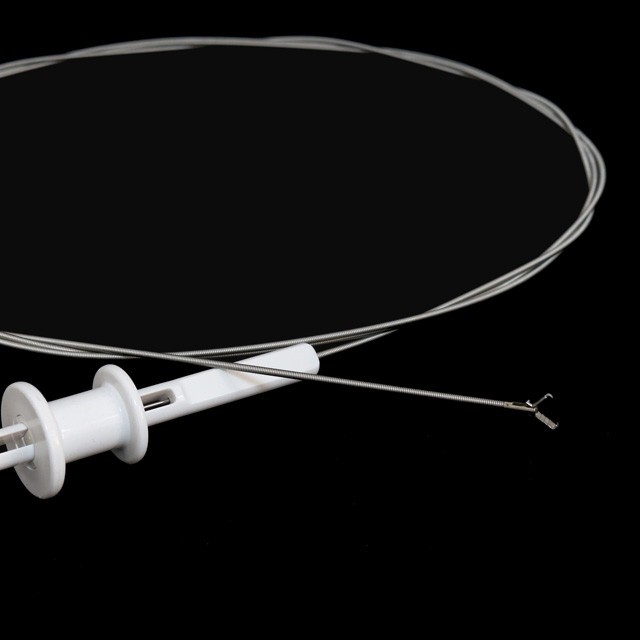

Icilangililo

FG{0{0}}U-B3 |

FG{0{0}}U-B4 |

FG{0{0}}U-B5 |

Umusango uushili

FG{0{0}}U{11}}D22 |

FG{0{0}}U{11}}D22 |